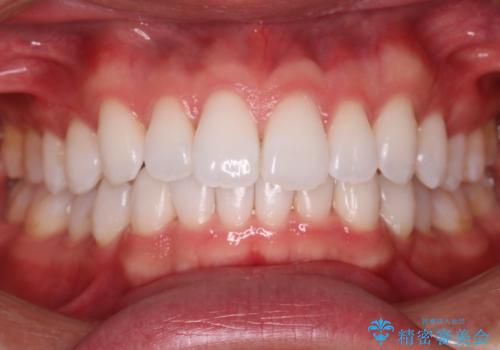

前歯のねじれ・ガタガタを10か月で改善!20代女性の矯正治療|クリアブラケットでむし歯になりにくい歯並びへ改善

担当医 齋藤佑磨

前歯のねじれ 矯正治療による歯並び改善